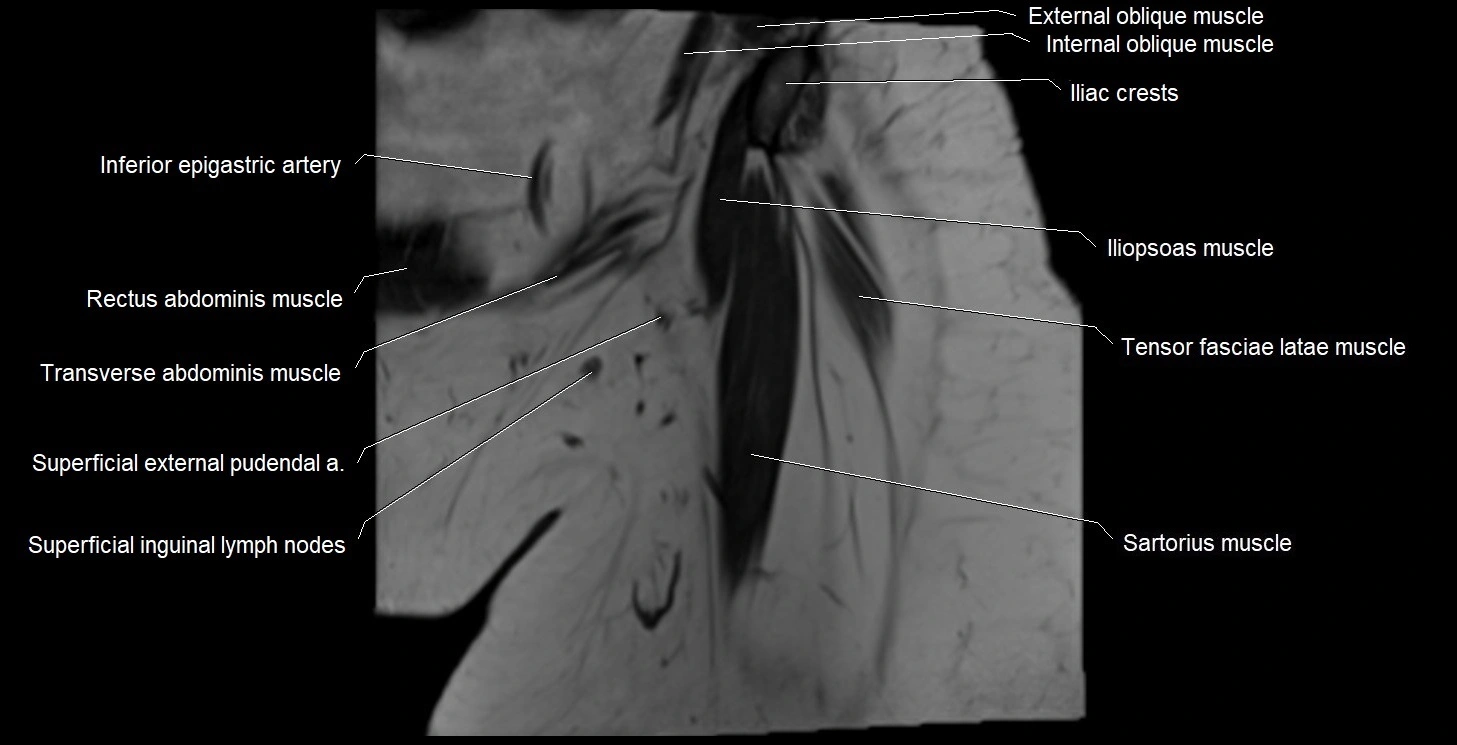

- Iliopsoas muscle

- Iliopsoas tendon

- Inferior epigastric artery

- Inferior epigastric veins

- Inguinal ligament

- Inguinal lymph nodes

- Sartorius muscle

- Superficial inguinal lymph nodes

- Tensor fasciae latae muscle